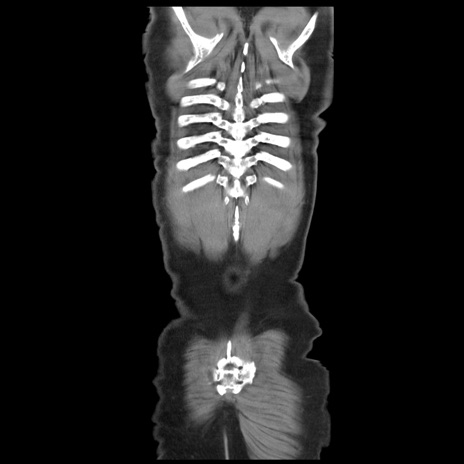

矢状断像

【症例】 60歳代男性

【主訴】 腹部膨満、嘔吐

【現病歴】5日前頃より倦怠感を認め食事量減少し4日前の朝嘔吐、食事摂取困難となった。 3日前近医受診し点滴施行され整腸剤などを処方された。 当日他院を受診し、腹部膨満著明、炎症反応の上昇(CRP10.8、WBC11200)あり、紹介受診となる。

【身体所見】 意識JCS1 受け答えがはっきりしないBP 111/57mHg、 P 67bpm、、BT35.2°C、SpO2 97%(RA)、 腹部:膨隆、打診で鼓音あり、全体的に圧痛有り、腸蠕動音(-)、反跳痛ははっきりせず。

【データ】WBC 11400、CRP 14.20